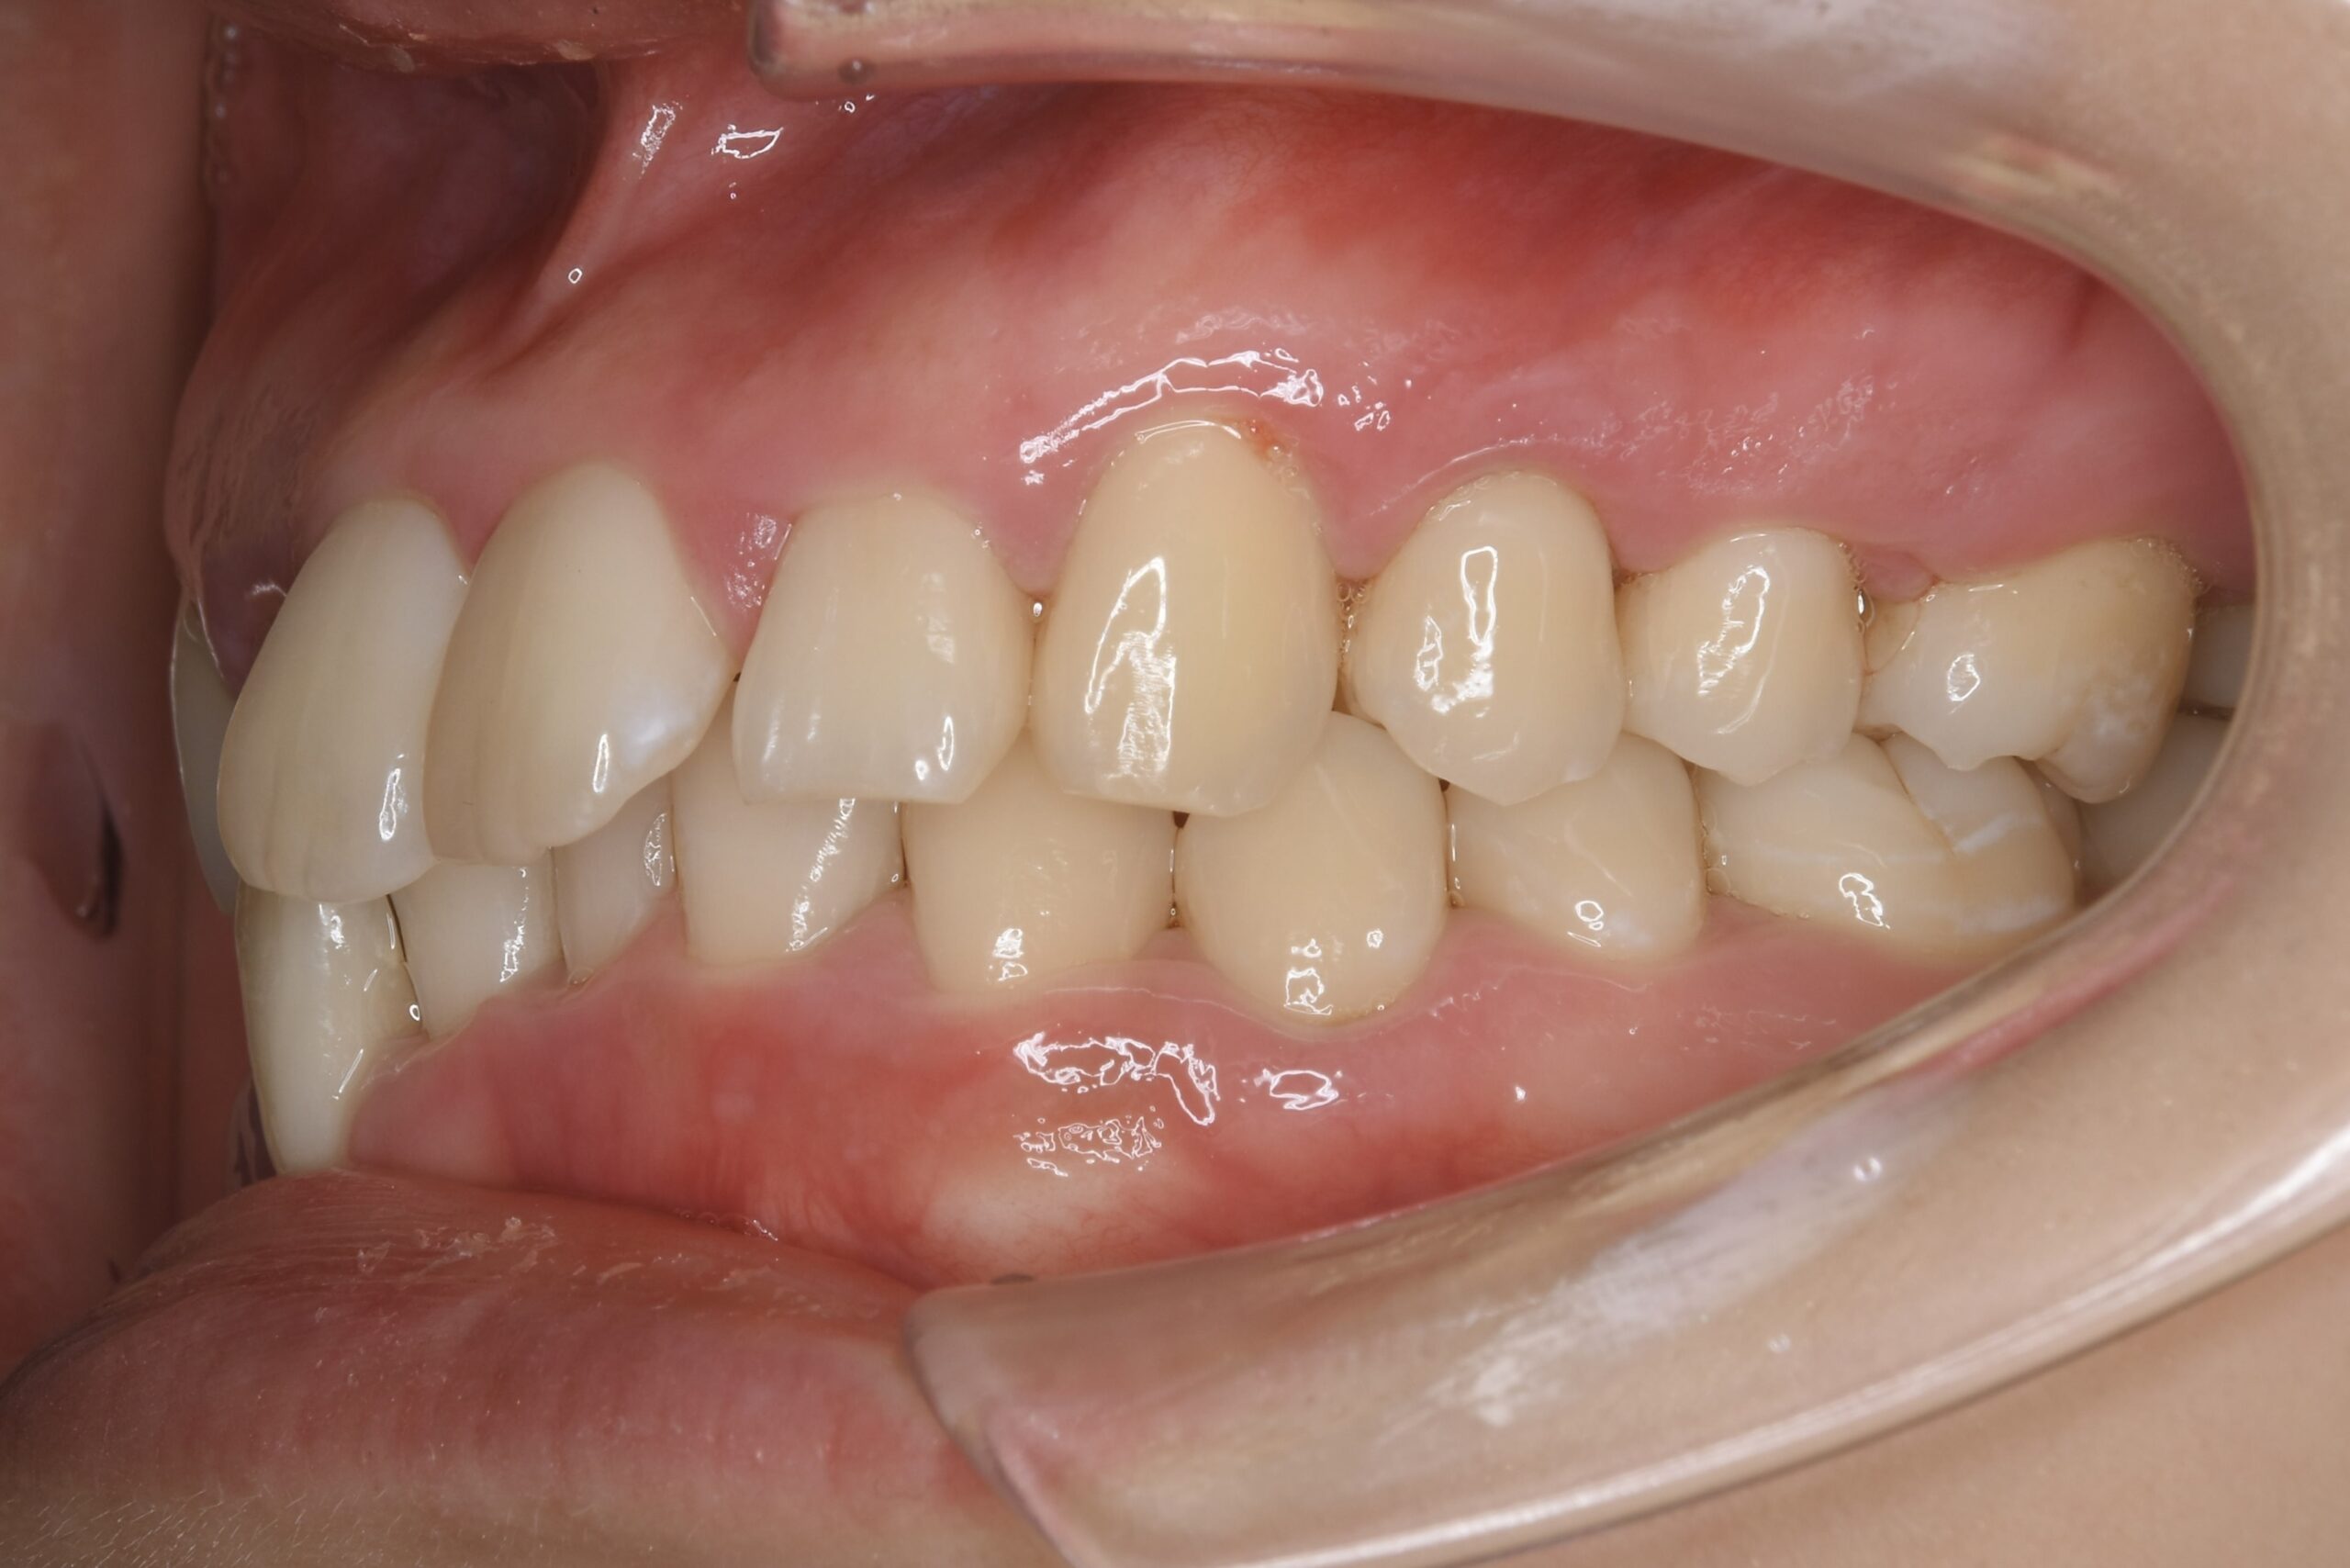

21歳 女性 治療期間:1年1ヶ月

叢生(ガタガタ)

マウスピース矯正装置(インビザライン)

BEFORE

AFTER

主訴

周りの人の歯並びが綺麗で自分の歯並びを治したくなってきた。

診断名・主な症状

叢生

治療内容

上下とも歯並びの横幅を広げながら、でこぼこを解消しました。

マウスピース矯正(インビザライン)

抜歯あり(智歯抜歯)

治療期間

1年1ヶ月

通院回数

10回

費用

85万円程度(税別)

リスク・副作用

痛み、歯肉退縮、歯根吸収、抜歯に伴う出血や腫れが生じることがあります。